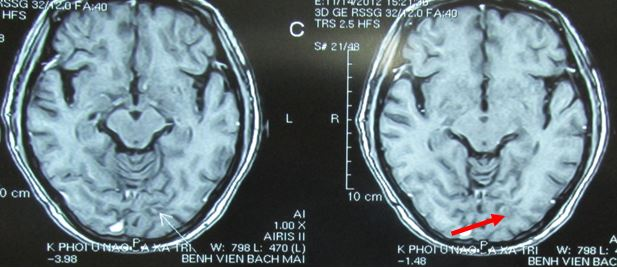

- Chụp MRI sọ não

Hình 2: hình ảnh chụp MRI sọ não cho thấy di căn não đa ổ

Hình 8: U di căn não đa ổ trước điều trị

Hình 9: tổn thương não tiêu biến hoàn toàn, lâm sàng hoàn toàn bình thường